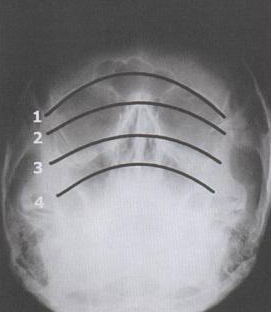

Waters View

Normal

Water Views

• Dolan Evaluation Method

• Four  Curvilinear To Observing For Asymmetry